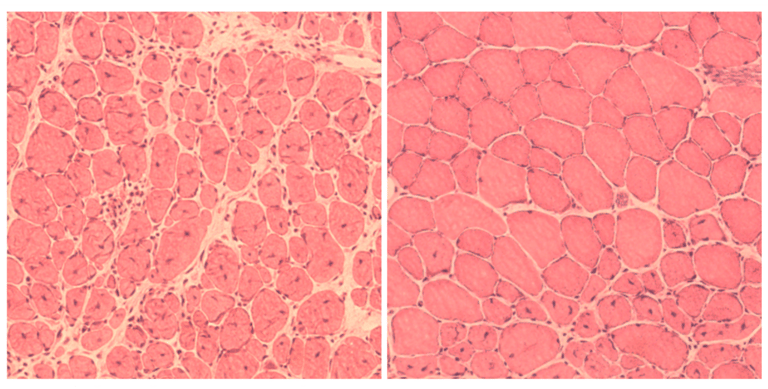

左邊是老鼠體內細胞修復前的模樣,右邊則是觸發基因後,細胞重組的狀況。